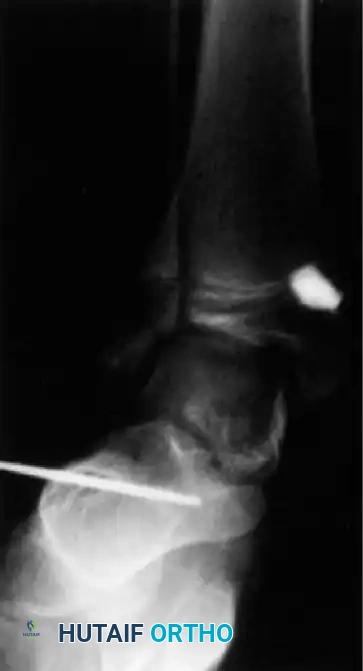

When conservative measures fail, surgical intervention is required:

1. Comprehensive Posteromedial Release (PMR): Involves lengthening of the Achilles, posterior tibialis, FDL, and FHL, along with extensive capsulotomies of the ankle, subtalar, and talonavicular joints.